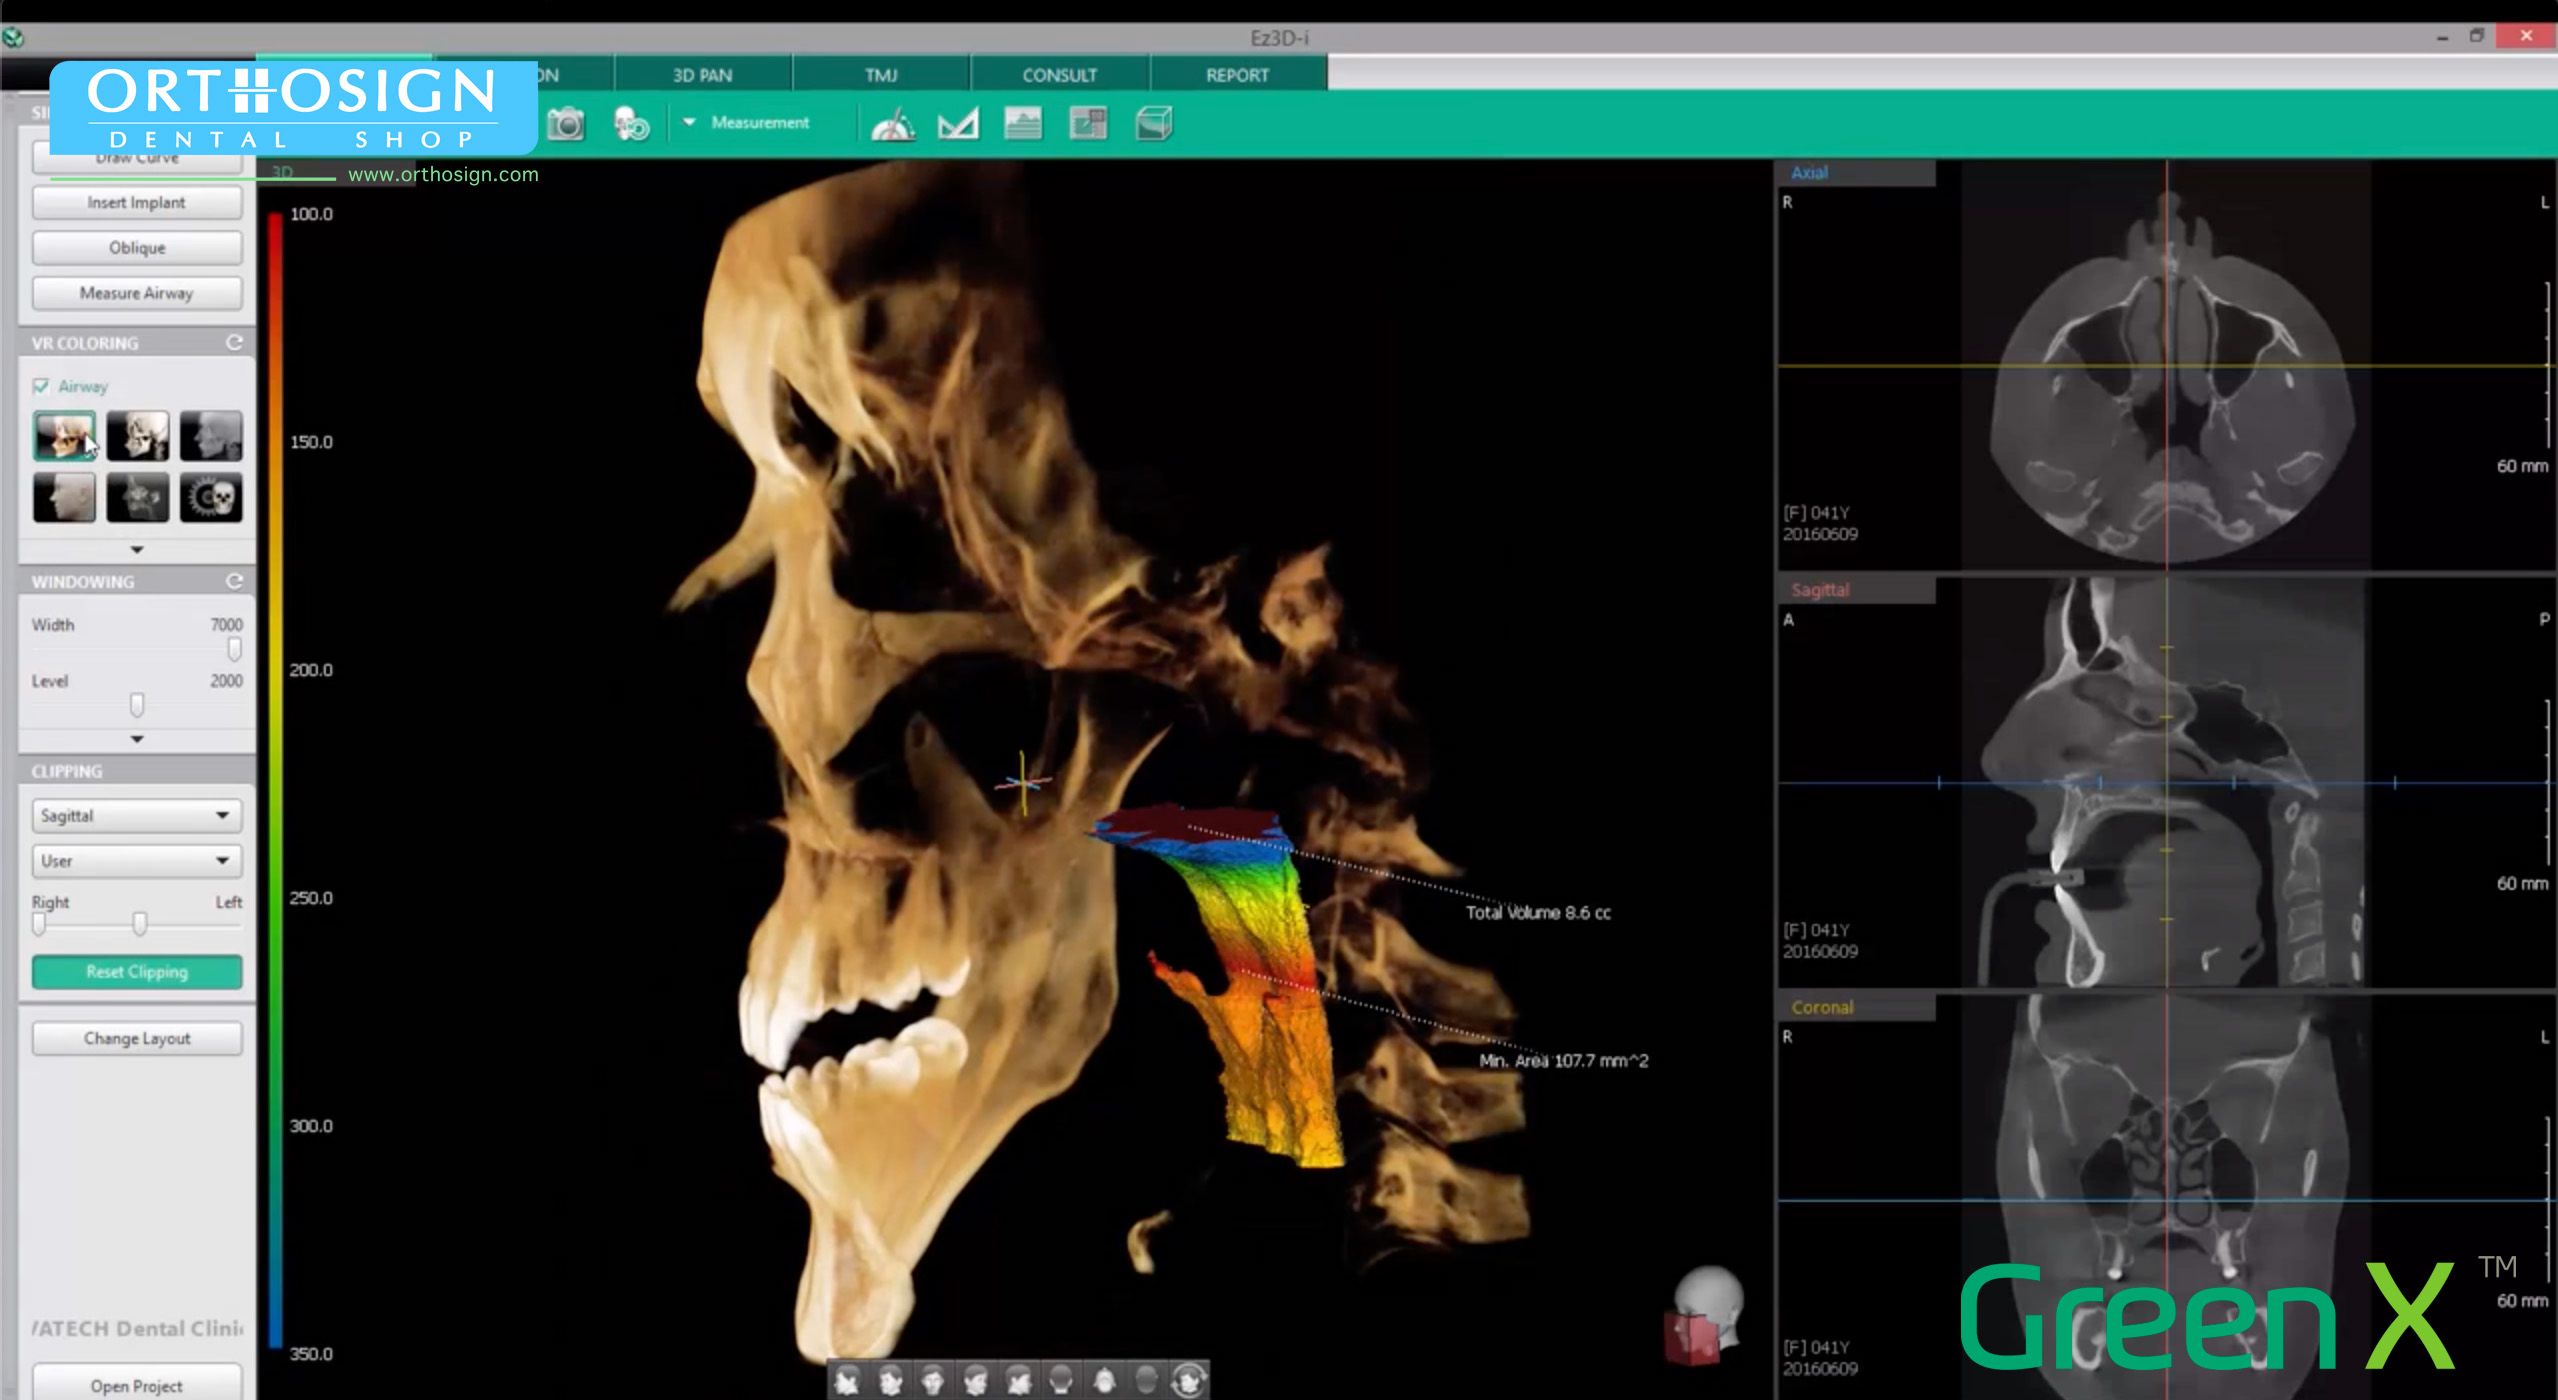

- CBCT, Cone Beam Computer Tomography. Imágenes en 3D de 18 x 24 cm.

- Radiografía de ATM.

- Radiografía de Senos Paranasales.